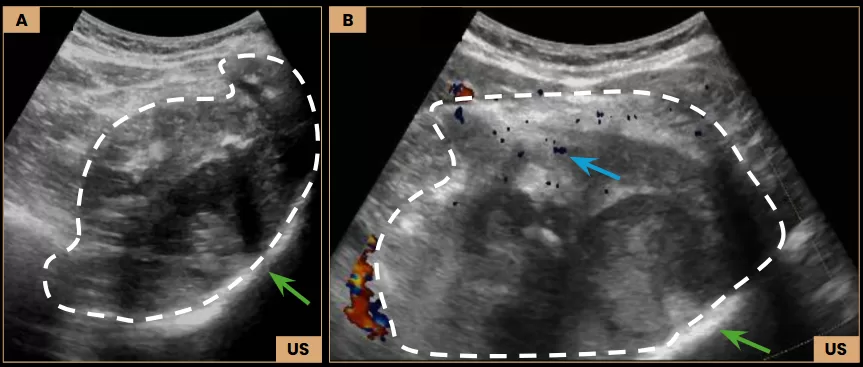

Images A and B: Ultrasound images show a large, heterogeneous expansile lesion (dashed line) located within the deep muscle planes and involving the left iliac bone (arrows – green), measuring 12.3 cm, with internal flow demonstrated on Doppler (arrow – blue).